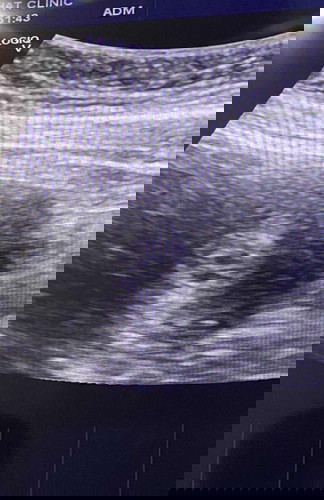

แม่ๆแบบนี้คือแฝดมั้ยค่ะ

5 สัปดาห์ 5 วันค่ะ